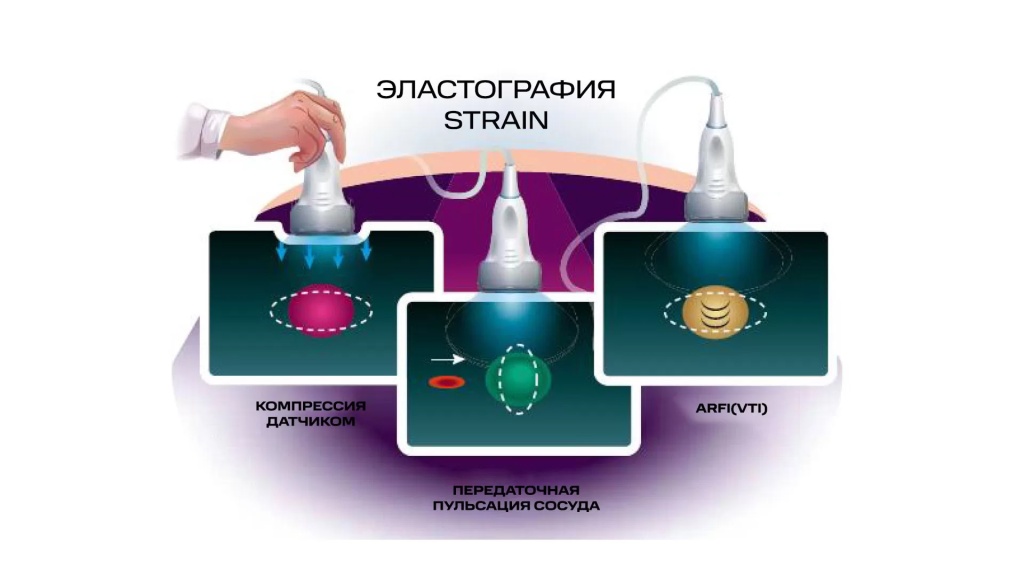

– Если не брать в расчет магнитно-резонансную эластографию и говорить только об ультразвуковой, то в зависимости от приложения силы, данный метод подразделяется на две большие группы: стрейновую эластографию (и наиболее распространенный ее вид – компрессионную) и эластографию сдвиговой волной.

В начале обсудим методику стрейновой эластографии. Она основана на сравнительной оценке деформации (или стрейнов) тканей в области интереса. Деформация может вызываться как приложенной мануальной компрессией, когда мы датчиком слегка надавливаем на подлежащие структуры, так и физиологическими явлениями – передаточной пульсацией сердца, сосудов, дыхательными движениями, а в некоторых случаях и усиленным акустическим импульсом.

В данном случае получение абсолютных значений модуля Юнга (характеризующего жесткость тканей) невозможно, так как его значения зависят от приложенной силы, величина которой не стандартизирована и неизвестна. Поэтому проводится сравнение величины деформации, или стрейна. При воздействии одинаковой силы менее деформируемые ткани являются более жесткими, а более деформируемые – менее жесткими. Ультразвуковой сканер, работающий в специальном режиме, позволяет оценить и сравнить величину деформации тканей в окне опроса и картировать их соответствующим цветом, а также провести полуколичественную оценку – определить отношение деформации в зоне интереса и референсной (условно здоровой) ткани – StrainRatio.